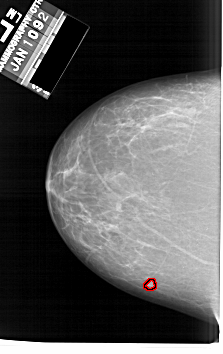

A_1634_1.LEFT_MLO

LEFT_MLO LINES 6271 PIXELS_PER_LINE 4291 BITS_PER_PIXEL 12 RESOLUTION 43.5 OVERLAY

FILE: A_1634_1.LEFT_MLO.OVERLAY

TOTAL_ABNORMALITIES 1

ABNORMALITY 1

LESION_TYPE MASS SHAPE LOBULATED MARGINS MICROLOBULATED

ASSESSMENT 4

SUBTLETY 4

PATHOLOGY BENIGN

TOTAL_OUTLINES 1

BOUNDARY